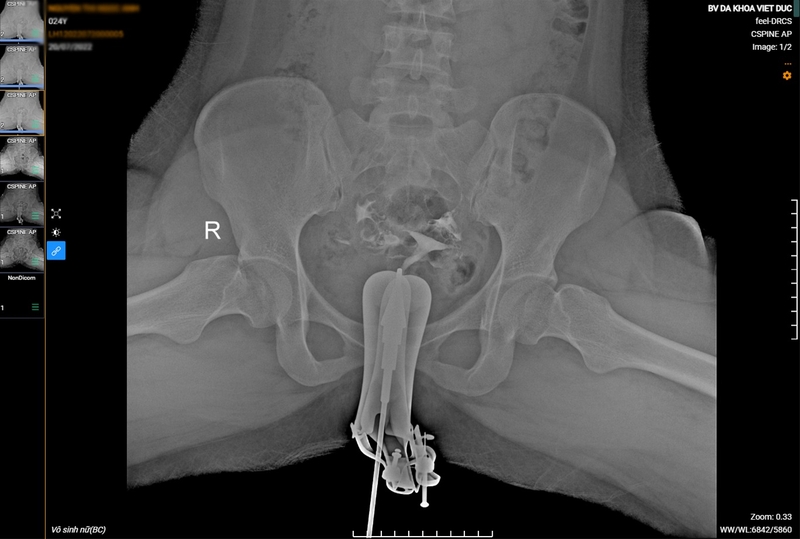

Chụp X quang tử cung vòi trứng là kỹ thuật dùng tia X để ghi lại các hình ảnh trong buồng trứng, tử cung, vòi trứng của người phụ nữ. Đây là kỹ thuật chẩn đoán hình ảnh lâu đời nhưng mang lại hiệu quả khá cao. Chụp X quang giúp các bác sĩ quan sát và đánh giá các phần cấu trúc trong cơ quan sinh dục nữ mà bình thường không thể quan sát bằng mắt thường.

Chụp X quang tử cung vòi trứng tương tự như chụp X quang thông thường, tuy nhiên cần dùng thêm thuốc cản quang được bơm vào buồng tử cung với áp lực thấp. Buồng tử cung có cấu tạo thông với hai vòi trứng. Nên khi bơm thuốc vào buồng tử cung, thuốc cũng sẽ chảy sang hai bên vòi trứng. Các bác sĩ sẽ căn cứ vào dòng lưu thông của thuốc cản quang trên hình ảnh chụp X quang tại các thời điểm khác nhau để xác định các bất thường ở cổ tử cung, buồng tử cung, vòi trứng, buồng trứng nếu có.

Chụp X quang tử cung vòi trứng là một kỹ thuật chẩn đoán bệnh đơn giản, ít tốn kém, ít tác dụng phụ nhưng lại có hiệu quả cao. Hình ảnh chụp X quang tử cung vòi trứng là căn cứ tin cậy để bác sĩ đánh giá sức khỏe sinh sản nữ giới.